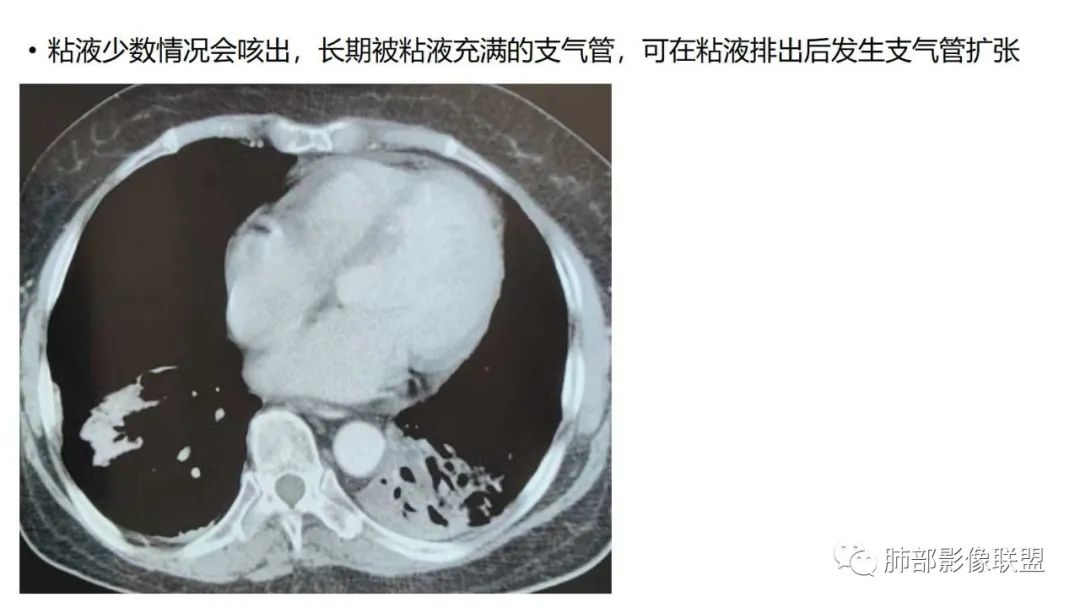

9.粘液腺癌的变化规律:结节缓慢发展而来,向周围播散形成斑片后可快速进展,有时支气管镜后或粘液排出后局部可形成好转的假象。病灶可沿肺泡和支气管播散。

4.回到本例,左下肺病变两次好转,均未经过肿瘤治疗,第一次是支气管镜后,第二次是当其他病变都在进展的情况下,左下肺病变范围反而缩小趋于浅淡。